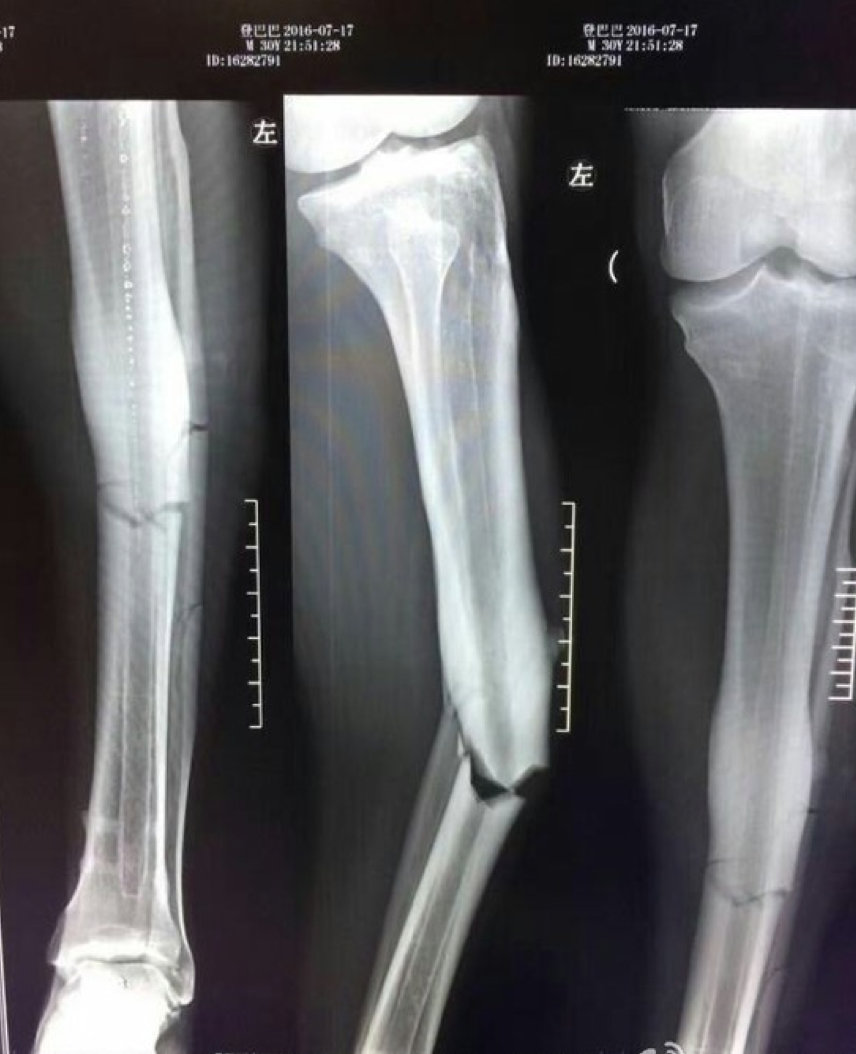

Voici les images radios, qui démontrent la blessure très spectaculaire de Demba Ba